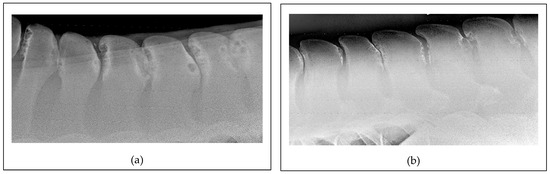

5.2. Diagnostic Imaging Findings